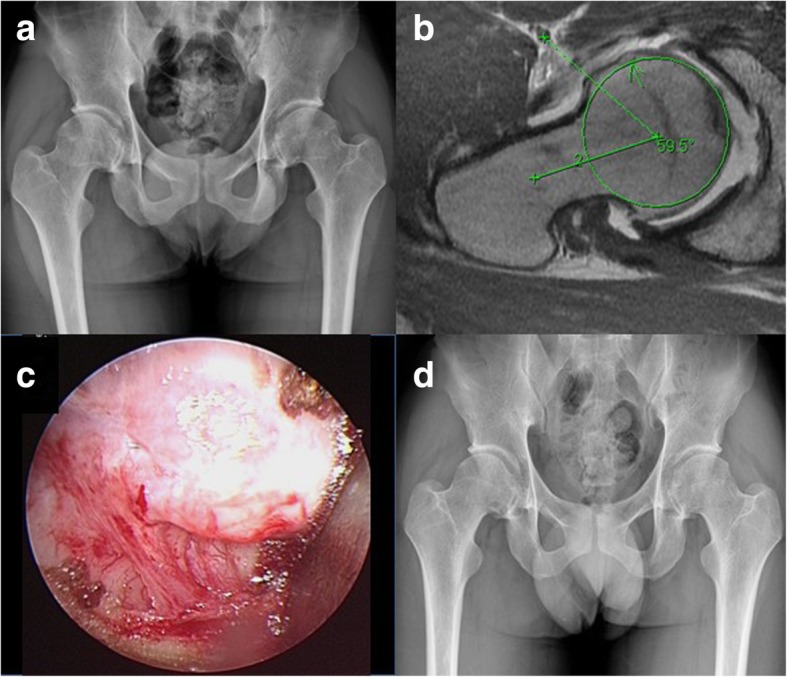

Fig. 2.

A 23-year-old male patient with bilateral proximal femur cam-type FAI. a Preoperative pelvis radiograph. b Preoperative right hip MRI axial view. c intraoperative arthroscopic image showing the bony bump. d Follow-up radiography of pelvis AP view at postoperative 3 years